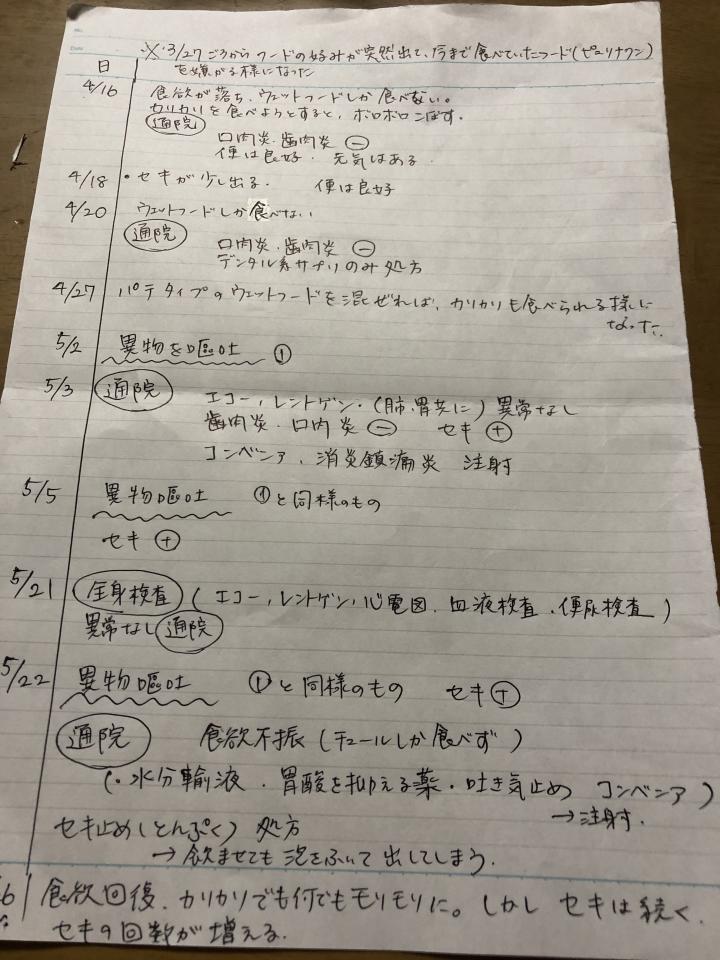

今までの経緯をまとめて記入して通院。

経過メモ

経過メモをまとめて病院に提出するために、ネコジルシで書かせていただいた日記が、大変役に立ちました!